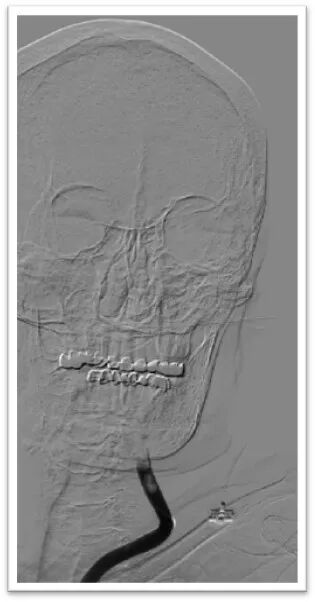

图4:DSA提示主动脉弓为牛角弓,左侧颈总动脉发自头臂干动脉,右侧颈内动脉造影提示前交通动脉开放,呈双干大脑前动脉,左侧大脑前动脉通过软膜支向左侧大脑中动脉供血区域代偿,双侧椎动脉均势供血,左侧大脑后动脉通过软膜支向前代偿供血;左侧颈总动脉闭塞,残端呈杯口状,近端可见白色血栓影,初步考虑栓塞性闭塞。